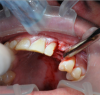

These data were used to fabricate the surgical guide and a temporary. Figure 9 shows the implant in place digitally. All the data and models were taken into account before surgery. The clinician received a 3D-printed model with the tooth extracted, a guide (Figure 10), and a healing cap and temporary (Figure 11). The latter two were required for initial stability of the implant to immediately provisionalize. The "bail-out clause" is the healing cap because if the implant cannot be immediately loaded, the healing cap can be placed instead. For this case, the patient's tooth was extracted and bone had been grafted several months previously. Figure 12 shows the patient's previous tooth bonded into place. The flap was laid (Figure 13) and the surgeon was given a set of instructions that come with every guided case.

Fig 13. The location was prepared by laying a flap.

Figure 13